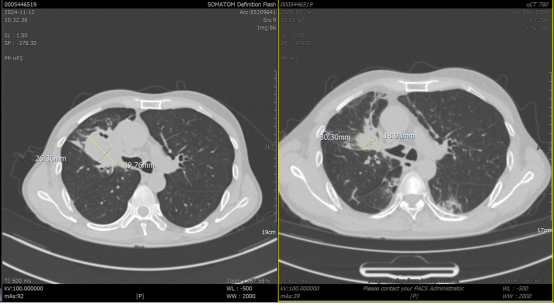

疗效评估:2025-3-24 放疗结束后1个月,行胸部CT平扫,对比放疗前(2024-11-12):右肺上叶恶性肿瘤伴纵隔、右肺门淋巴结转移治疗后复查,较前肿块及淋巴结、上叶阻塞性肺炎范围有所缩小。